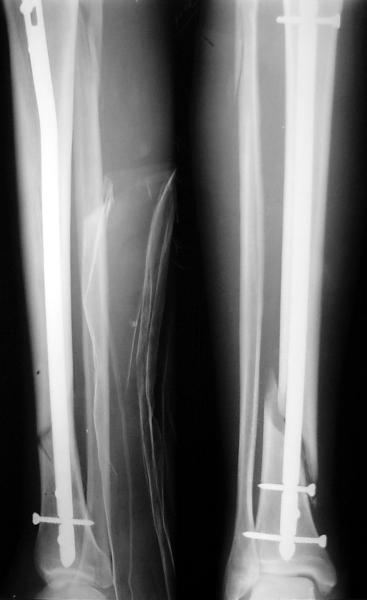

На мой взгляд, на снимках, приведённых Вами - неправильно сростающийся перелом дистальной трети большеберцовой кости, состояние после остеосинтеза интрамедуллярным гвоздём.

Как Вы пишите снимок под номером 1 - менсяц после операции, под номером 2- два месяца после операции.

Вы не послали послеоперационный снимок, поэтому трудно судить о состоянии редукции после операции.

Позвольте по поводу техники операции высказать своё мнение...

Установка с медиальной стороны гвоздя в области дистального фрагмента дополнительного шурупа помогло бы Вам репонировать и удержать перелом в анатомическом положении, предотвратило варусную деформацию и смещение по ширине.

Кстати, если можно пошлите послеоперационный снимок.

На мой взгляд внутрикостная фиксация переломов дистальной и проксимальной трети большеберцовой кости, за исключением поперечных, не очень хорошее решение вопроса, аппарат Илизарова или Тэйлора, позволяющие призвести закрытую анатомическую редукцию и отличное удержание отломков в период сращения.

Пример, приведённый Вами в нашей дискуссии по времени нагрузки после остеосинтеза не совсем удачный... Ваш больной имеет счастье, что первым согнулся проксимальный замыкающий винт, а не дистальный и гвоздь не пенетрировал голеностопный сустав.

Ok. А также и следующий, в 3 месяца.